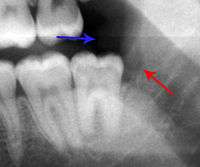

Lateral periodontal abscess (blue arrows) due to a fracture (green arrows)

A periodontal abscess (lateral abscess) is a collection of pus that forms in the gingival crevices, usually as a result of chronic periodontitis where the pockets are pathologically deepened greater than 3mm. A healthy gingival pocket will contain bacteria and some calculus kept in check by the immune system. As the pocket deepens, the balance is disrupted, and an acute inflammatory response results, forming pus. The debris and swelling then disrupt the normal flow of fluids into and out of the pocket, rapidly accelerating the inflammatory cycle. Larger pockets also have a greater likelihood of collecting food debris, creating additional sources of infection.[20]:443

Periodontal abscesses are less common than apical abscesses, but are still frequent. The key difference between the two is that the pulp of the tooth tends to be alive, and will respond normally to pulp tests. However, an untreated periodontal abscess may still cause the pulp to die if it reaches the tooth apex in a periodontic-endodontic lesion. A periodontal abscess can occur as the result of tooth fracture, food packing into a periodontal pocket (with poorly shaped fillings), calculus build-up, and lowered immune responses (such as in diabetes). Periodontal abscess can also occur after periodontal scaling, which causes the gums to tighten around the teeth and trap debris in the pocket.[20]:444–445 Toothache caused by a periodontal abscess is generally deep and throbbing. The oral mucosa covering an early periodontal abscess appears erythematous (red), swollen, shiny, and painful to touch.[21]